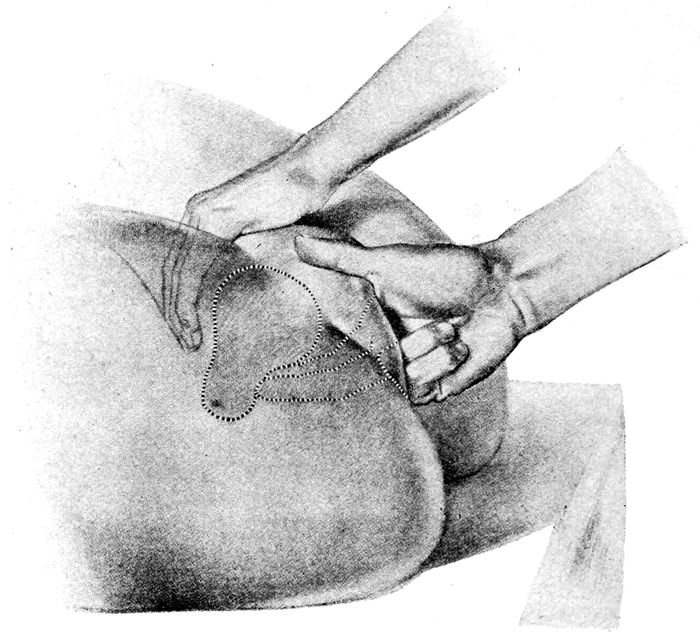

Fig. 26.—Bimanual examination. (Edgar.)